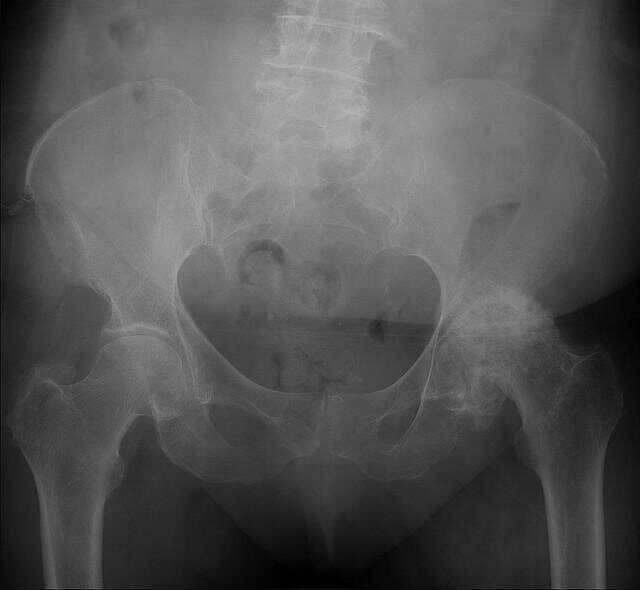

当时医院检查双侧股骨头坏死,建议手术,患者不接受,于是朋友介绍找到我。